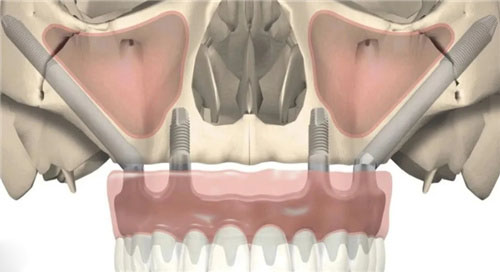

穿颧穿翼种植牙作为一种可靠的牙科手术技术,近年来在口腔医学领域逐渐受到关注。这种技术通过在上颌骨质疏松区域,利用高精度的3D打印导板辅助,将人工牙根直接固定于坚硬的颧骨或翼突区骨骼结构上,为那些因牙槽骨条件不佳而难以进行传统种植牙的患者提供了新的希望。然而,关于穿颧穿翼种植牙的可靠性问题,却一直是患者和医生关注的焦点。

然而,穿颧穿翼种植牙的可靠性并非肯定。由于手术难度大,风险也相对较高,对医生的技术要求非常高。手术区邻近面部动脉、静脉和神经,稍有不慎就可能导致出血、损伤神经等重度并发症。因此,患者在选择穿颧穿翼种植牙时,应充分了解手术风险,并选择正规口腔医院和经验充足的医生进行手术,以确保手术结果和患者的健康。